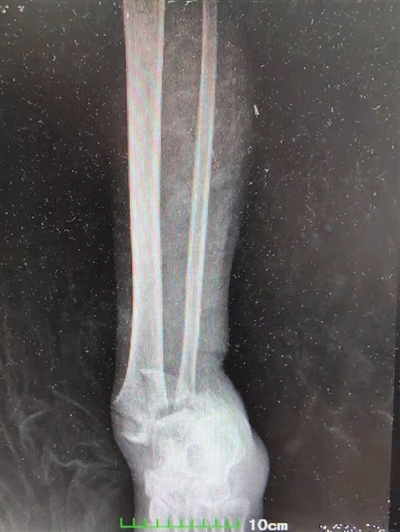

据刘先生介绍,今年9月中旬,他驾车外出途中不慎遭遇车祸伤及左足踝部,以为只是踝关节挤压了一下,休息一下就好。谁知近一个小时的时间后,刘先生左足踝关节不仅没有好转的迹象,反而疼痛持续加剧,被家人紧急送医。市第一人民医院骨外科主任刘昌余接诊后,立即为刘先生完善了相关检查。根据CT检查结果,诊断刘先生为为左踝关节Pinon骨折,如果不赶快进行救治,将落下终身残疾。

由于pilon骨折是指累及胫距关节面的胫骨远端骨折。而刘先生属于于pilon骨折中Ⅲ型,即关节面粉碎移位及粉碎程度较严重,手术难度较大,该科立即电话联系了武汉中南医院足踝外科中心主任祝少博,并组织专家通过远程与其进行了科内会诊、讨论,确定了在局部麻醉下先期为患者行跟骨牵引,并进行骨科常规护理、给予止血、消肿、止痛,待踝关节肿胀减轻后再行左胫腓骨下段粉碎性骨折开放复位钢板螺钉内固定术的整体方案。